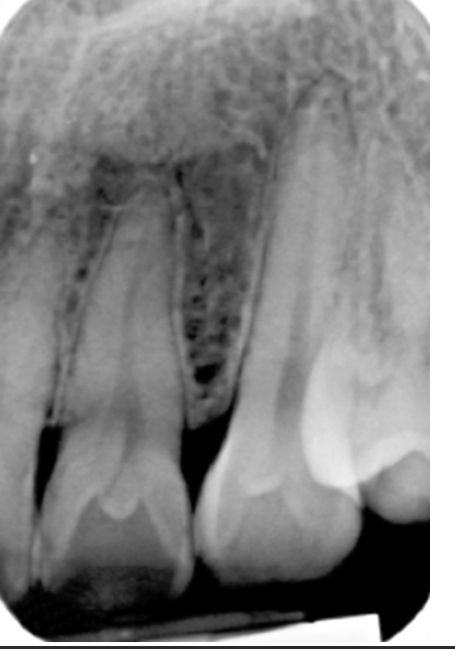

<p>4. Using Fig. 5.24, what would you call the enamel projections seen on the maxillary molars?</p><p>a. Enamel pearl</p><p>b. Enamel projection</p><p>c. Hypercementosis</p><p>d. Dens in dente</p>

4. Using Fig. 5.24, what would you call the enamel projections seen on the maxillary molars?

a. Enamel pearl

<p>42. What is seen in the radiograph (Fig. 5.28) on tooth #7?</p><p>a. Peg lateral</p><p>b. Dens in dente</p><p>c. Supernumerary tooth</p><p>d. Bifurcated root</p>

42. What is seen in the radiograph (Fig. 5.28) on tooth #7?

b. Dens in dente